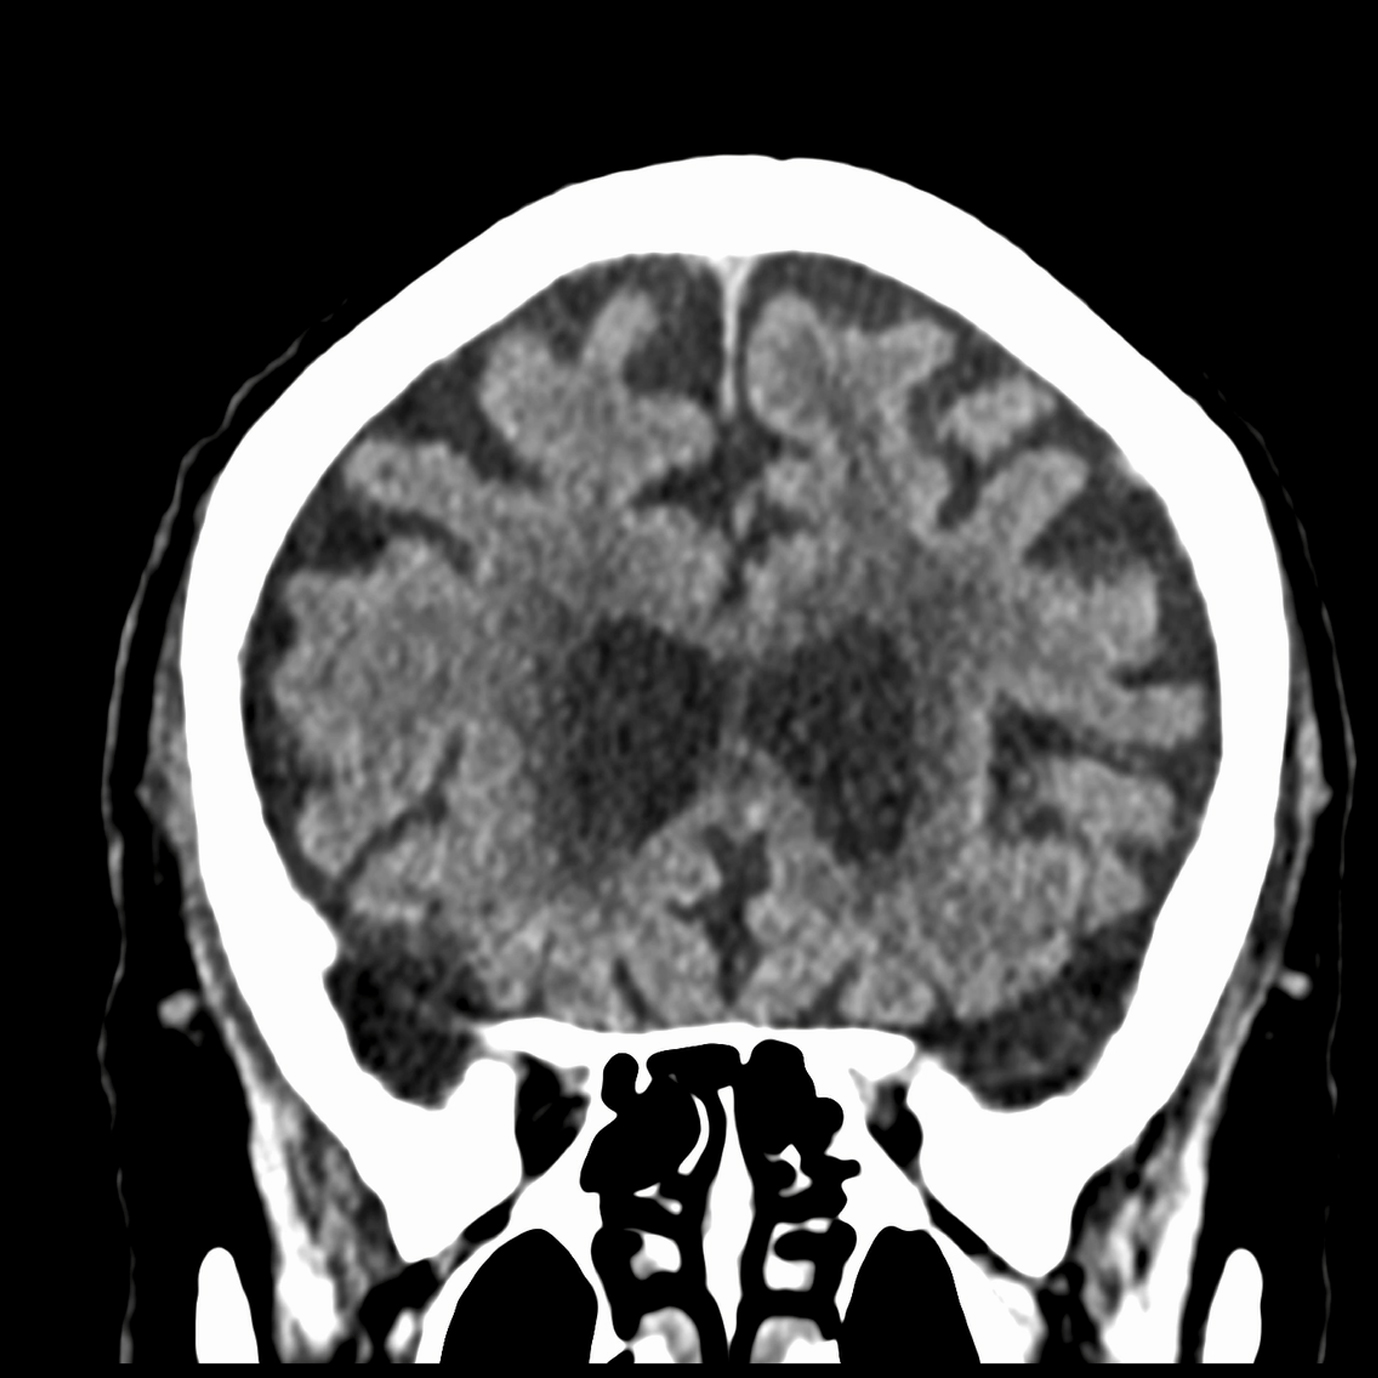

Ejemplos de estudios realizados en nuestra clínica.

con precisión avanzada para un diagnóstico confiable